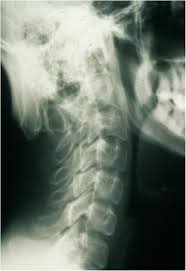

Radiographs of patients with classical MD show specific abnormalities: generalized osteoporosis, metaphyseal flaring and spurs in the long bones, diaphyseal periosteal reaction and thickening, and Wormian bones in the cranial sutures. Rib fracture due to osteoporosis is a common finding. In OHS patients occipital horns are characteristic radiographic findings. They continue to grow up to early adulthood.